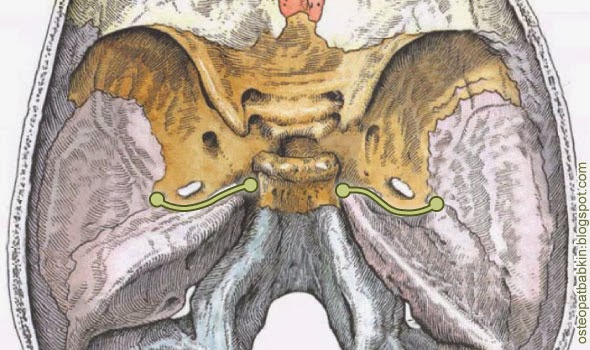

Структура и анатомия синдесмоза: научные иллюстрации